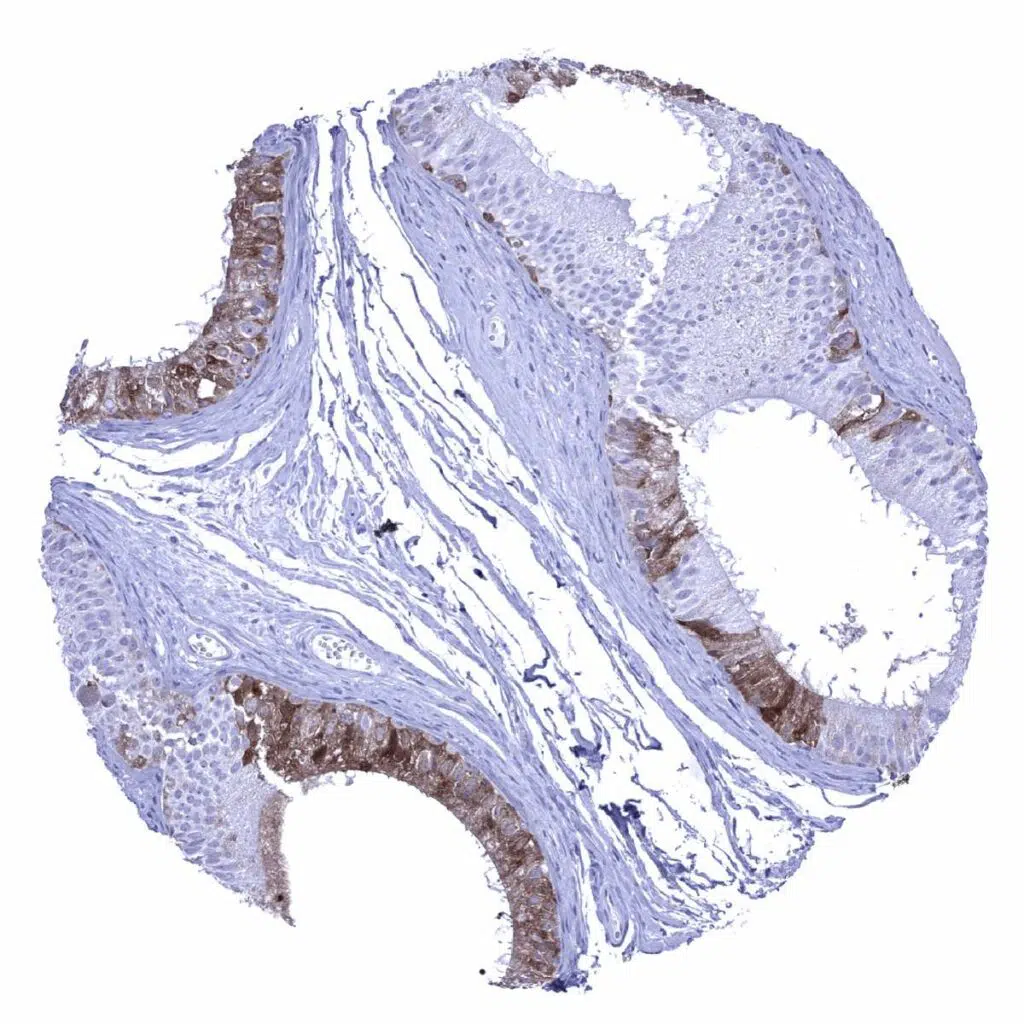

Esophagus, squamous epithelium – A moderate to strong nuclear and cytoplasmic GS staining occurs in the basal and suprabasal cell layers as well as in the top cell layers of the squamous epithelium.